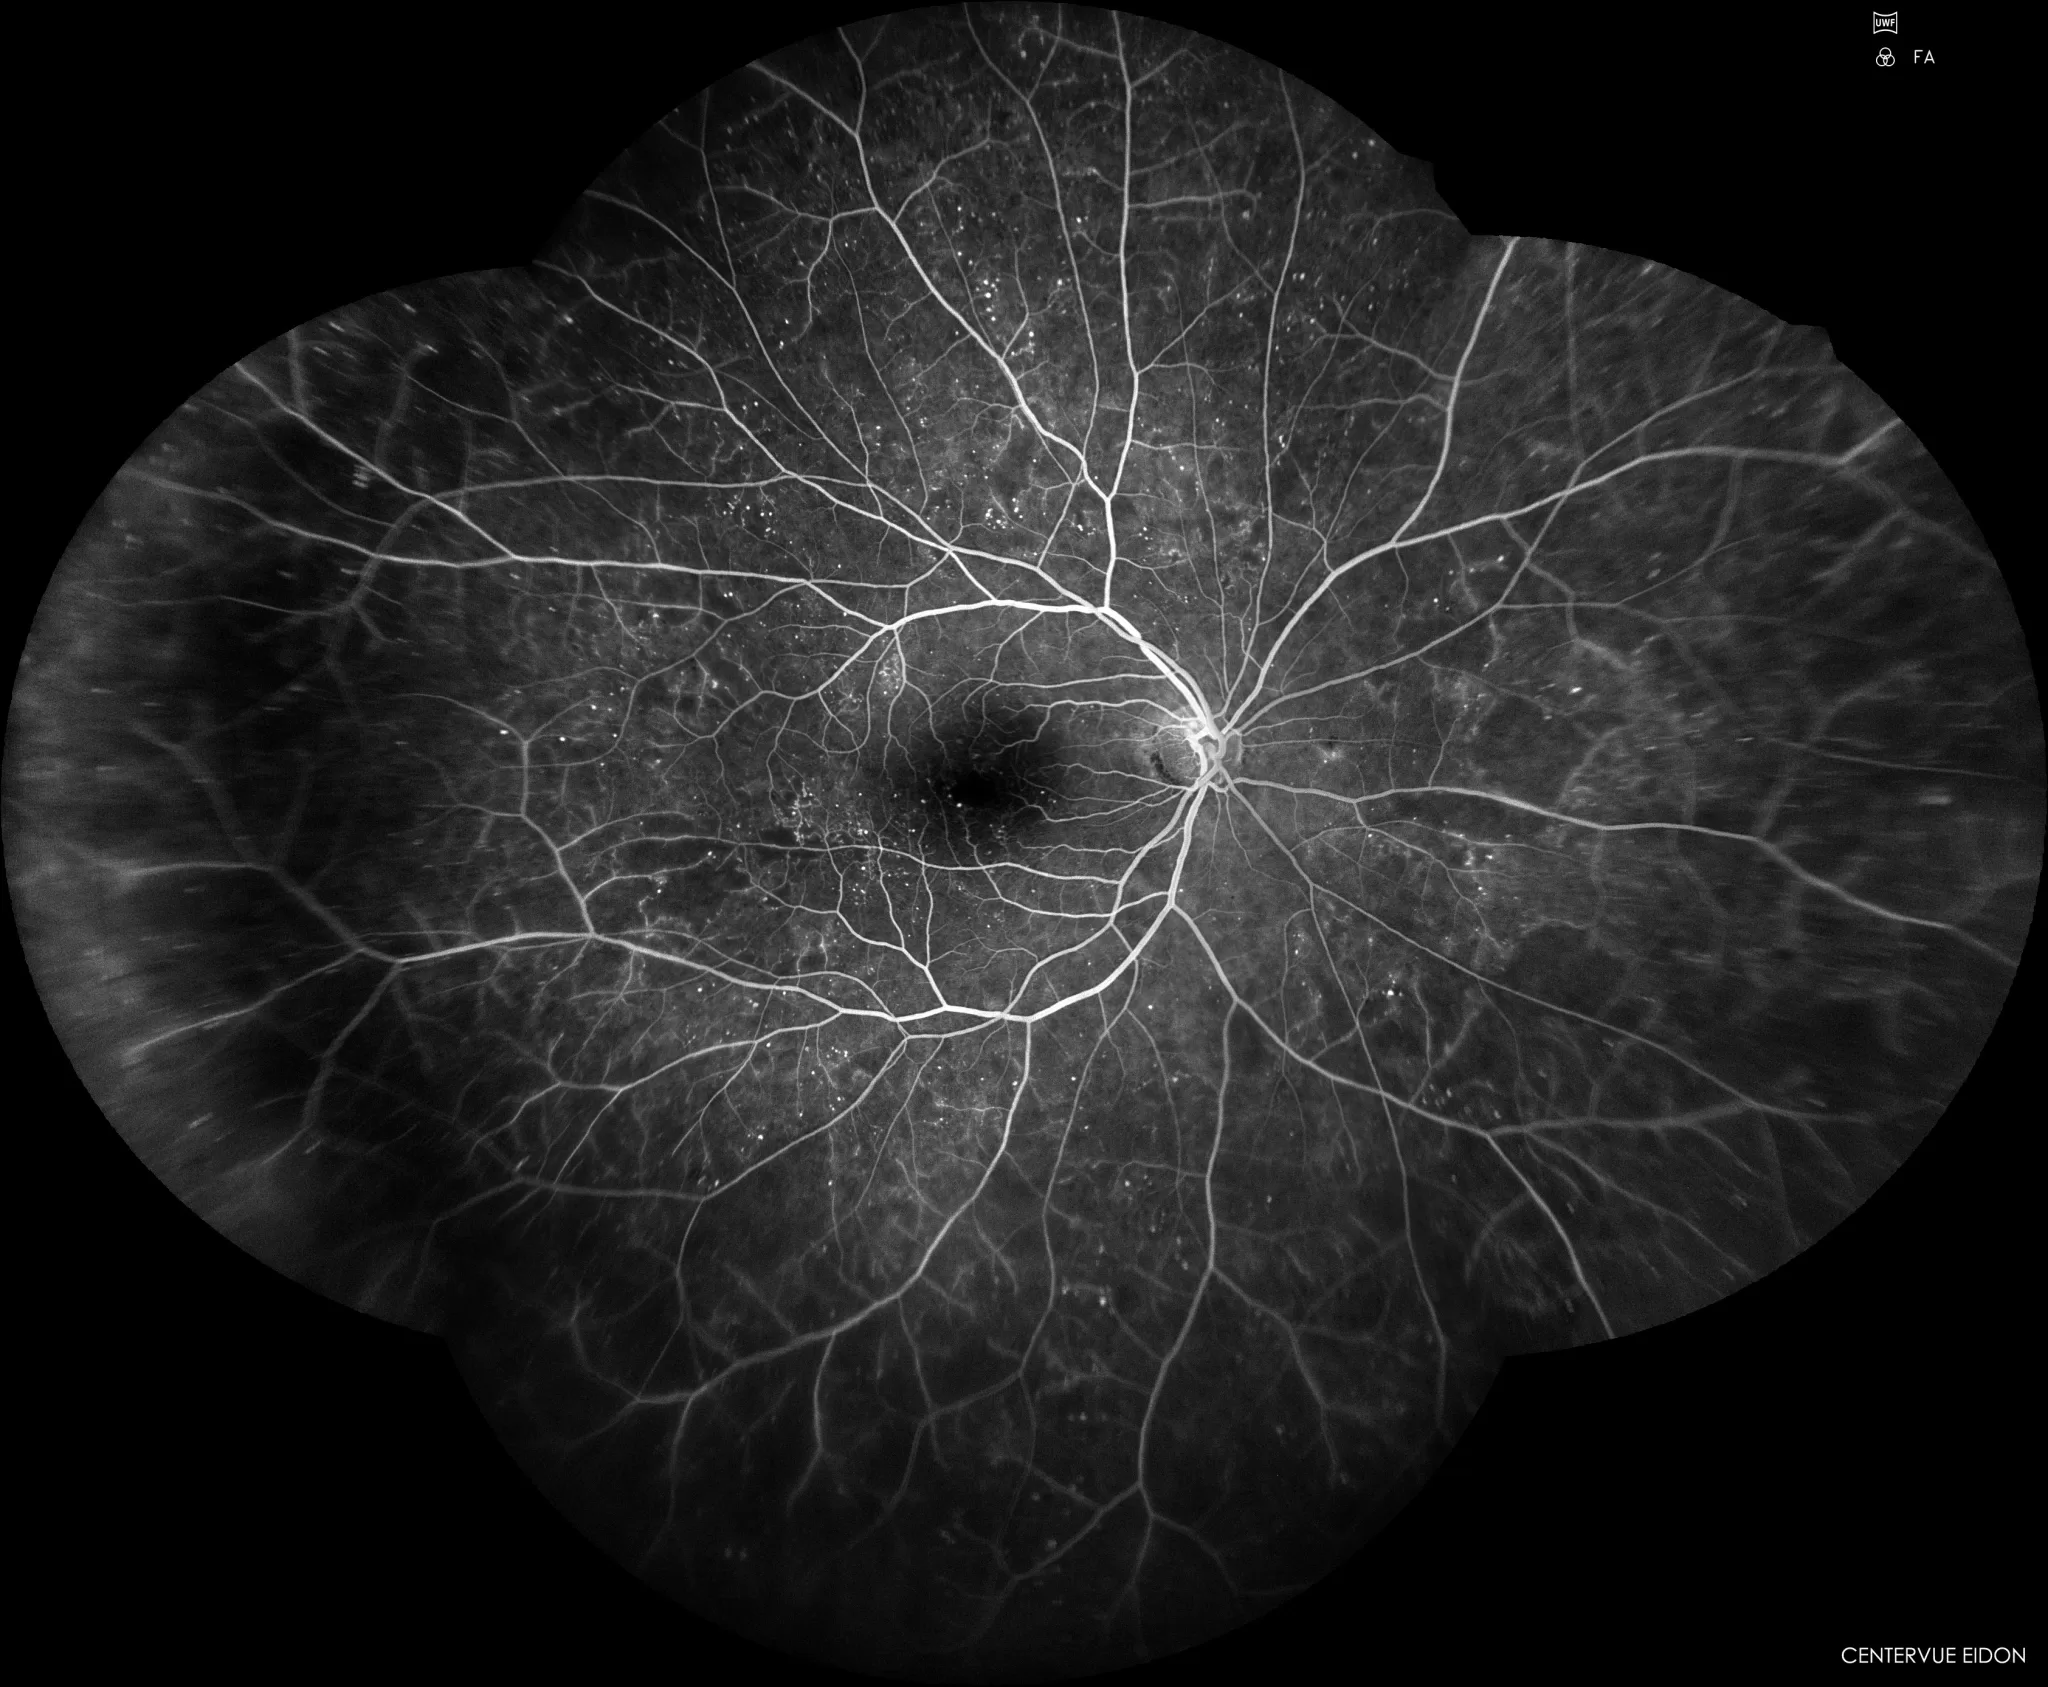

Hoje vamos falar do Retinógrafo de campo ultra-amplo (ultra-widefield). Este sofisticado instrumento faz fotografia da retina, sem dilatação da pupila, com uma resolução altíssima.

Figura 1 Retinografia da retina

Na Retinografia o diâmetro da pupila é um fator condicionante da amplitude da fotografia do Fundo Ocular. O retinógrafo de campo ultra-amplo usa um sistema com captação de imagem sem dilatação até 200°, ou seja, aproxima-se de 82% da retina, portanto uma área excecionalmente extensa. Emprega tecnologia de laser cSLO - Coherent scanning laser oftalmoscope, que permite fotografar a retina através de pupilas pequenas e com 3 gamas de laser, azul, verde e vermelho, a incidir nas camadas mais externa, média e interna que pode dividir as imagens em três camadas diferentes, das mais superficiais às mais  profundas, sempre com uma resolução altíssima.

A imagem composta assemelha-se a projeção do Globo terrestre num mapa, mas aqui estamos a colocar num plano o interior do olho e não o exterior da crosta terrestre.

Executa também a Angiografia  Fluoresceínica de campo ultra-amplo e permite também realizar exame de autofluorescência e infravermelho. É um instrumento polivalente e as possibilidades do uso são imensas e ultrapassam a Retinografia convencional e a Retinografia com  OCT que já usávamos.

Figura 10 Angiografia Fluoresceinica de campo ultra amplo

Figura 10 Angiografia Fluoresceínica de campo ultra-amplo